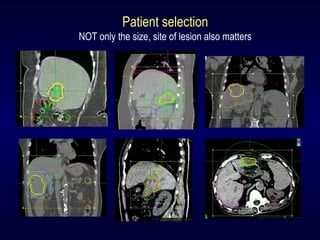

Patient selection

NOT only the size, site of lesion also matters

Outcome depends not ONLY on planning

BUT also on execution

Need internal fiducial based intra-fraction

tracking system

To treat liver tumour